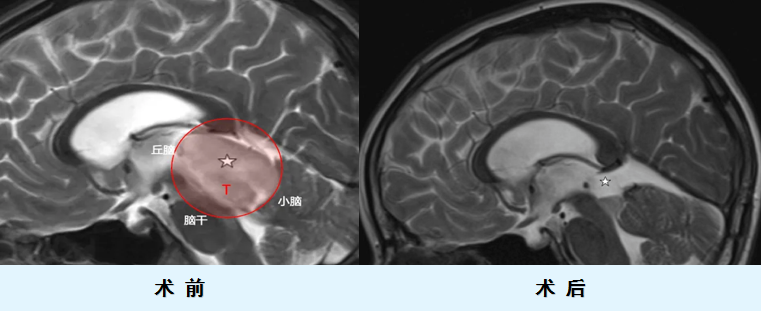

11岁的欢欢因连续的头痛和复视被诊断出一个巨大的中线肿瘤,侵袭丘脑、中脑顶盖(四叠体),从小脑延伸到松果体,并侵犯间脑,压迫双侧外展神经,眼底检查还发现伴随双侧视乳头水肿。

整个手术方案大致分成两步,首先,为了解决脑积水问题,两位教授先进行了内镜脑室造瘘术,然后采用枕下正中小脑上入路进行手术,最终成功切除肿瘤。

术后,欢欢短暂地出现一过性垂直性眼震,但在手术后的14天内完全恢复,并开始了后续的质子治疗和替莫唑胺治疗。这一台由两位国际大咖联手的手术获得极大的成功,也让欢欢能以较好的身体素质开展后续的辅助治疗。